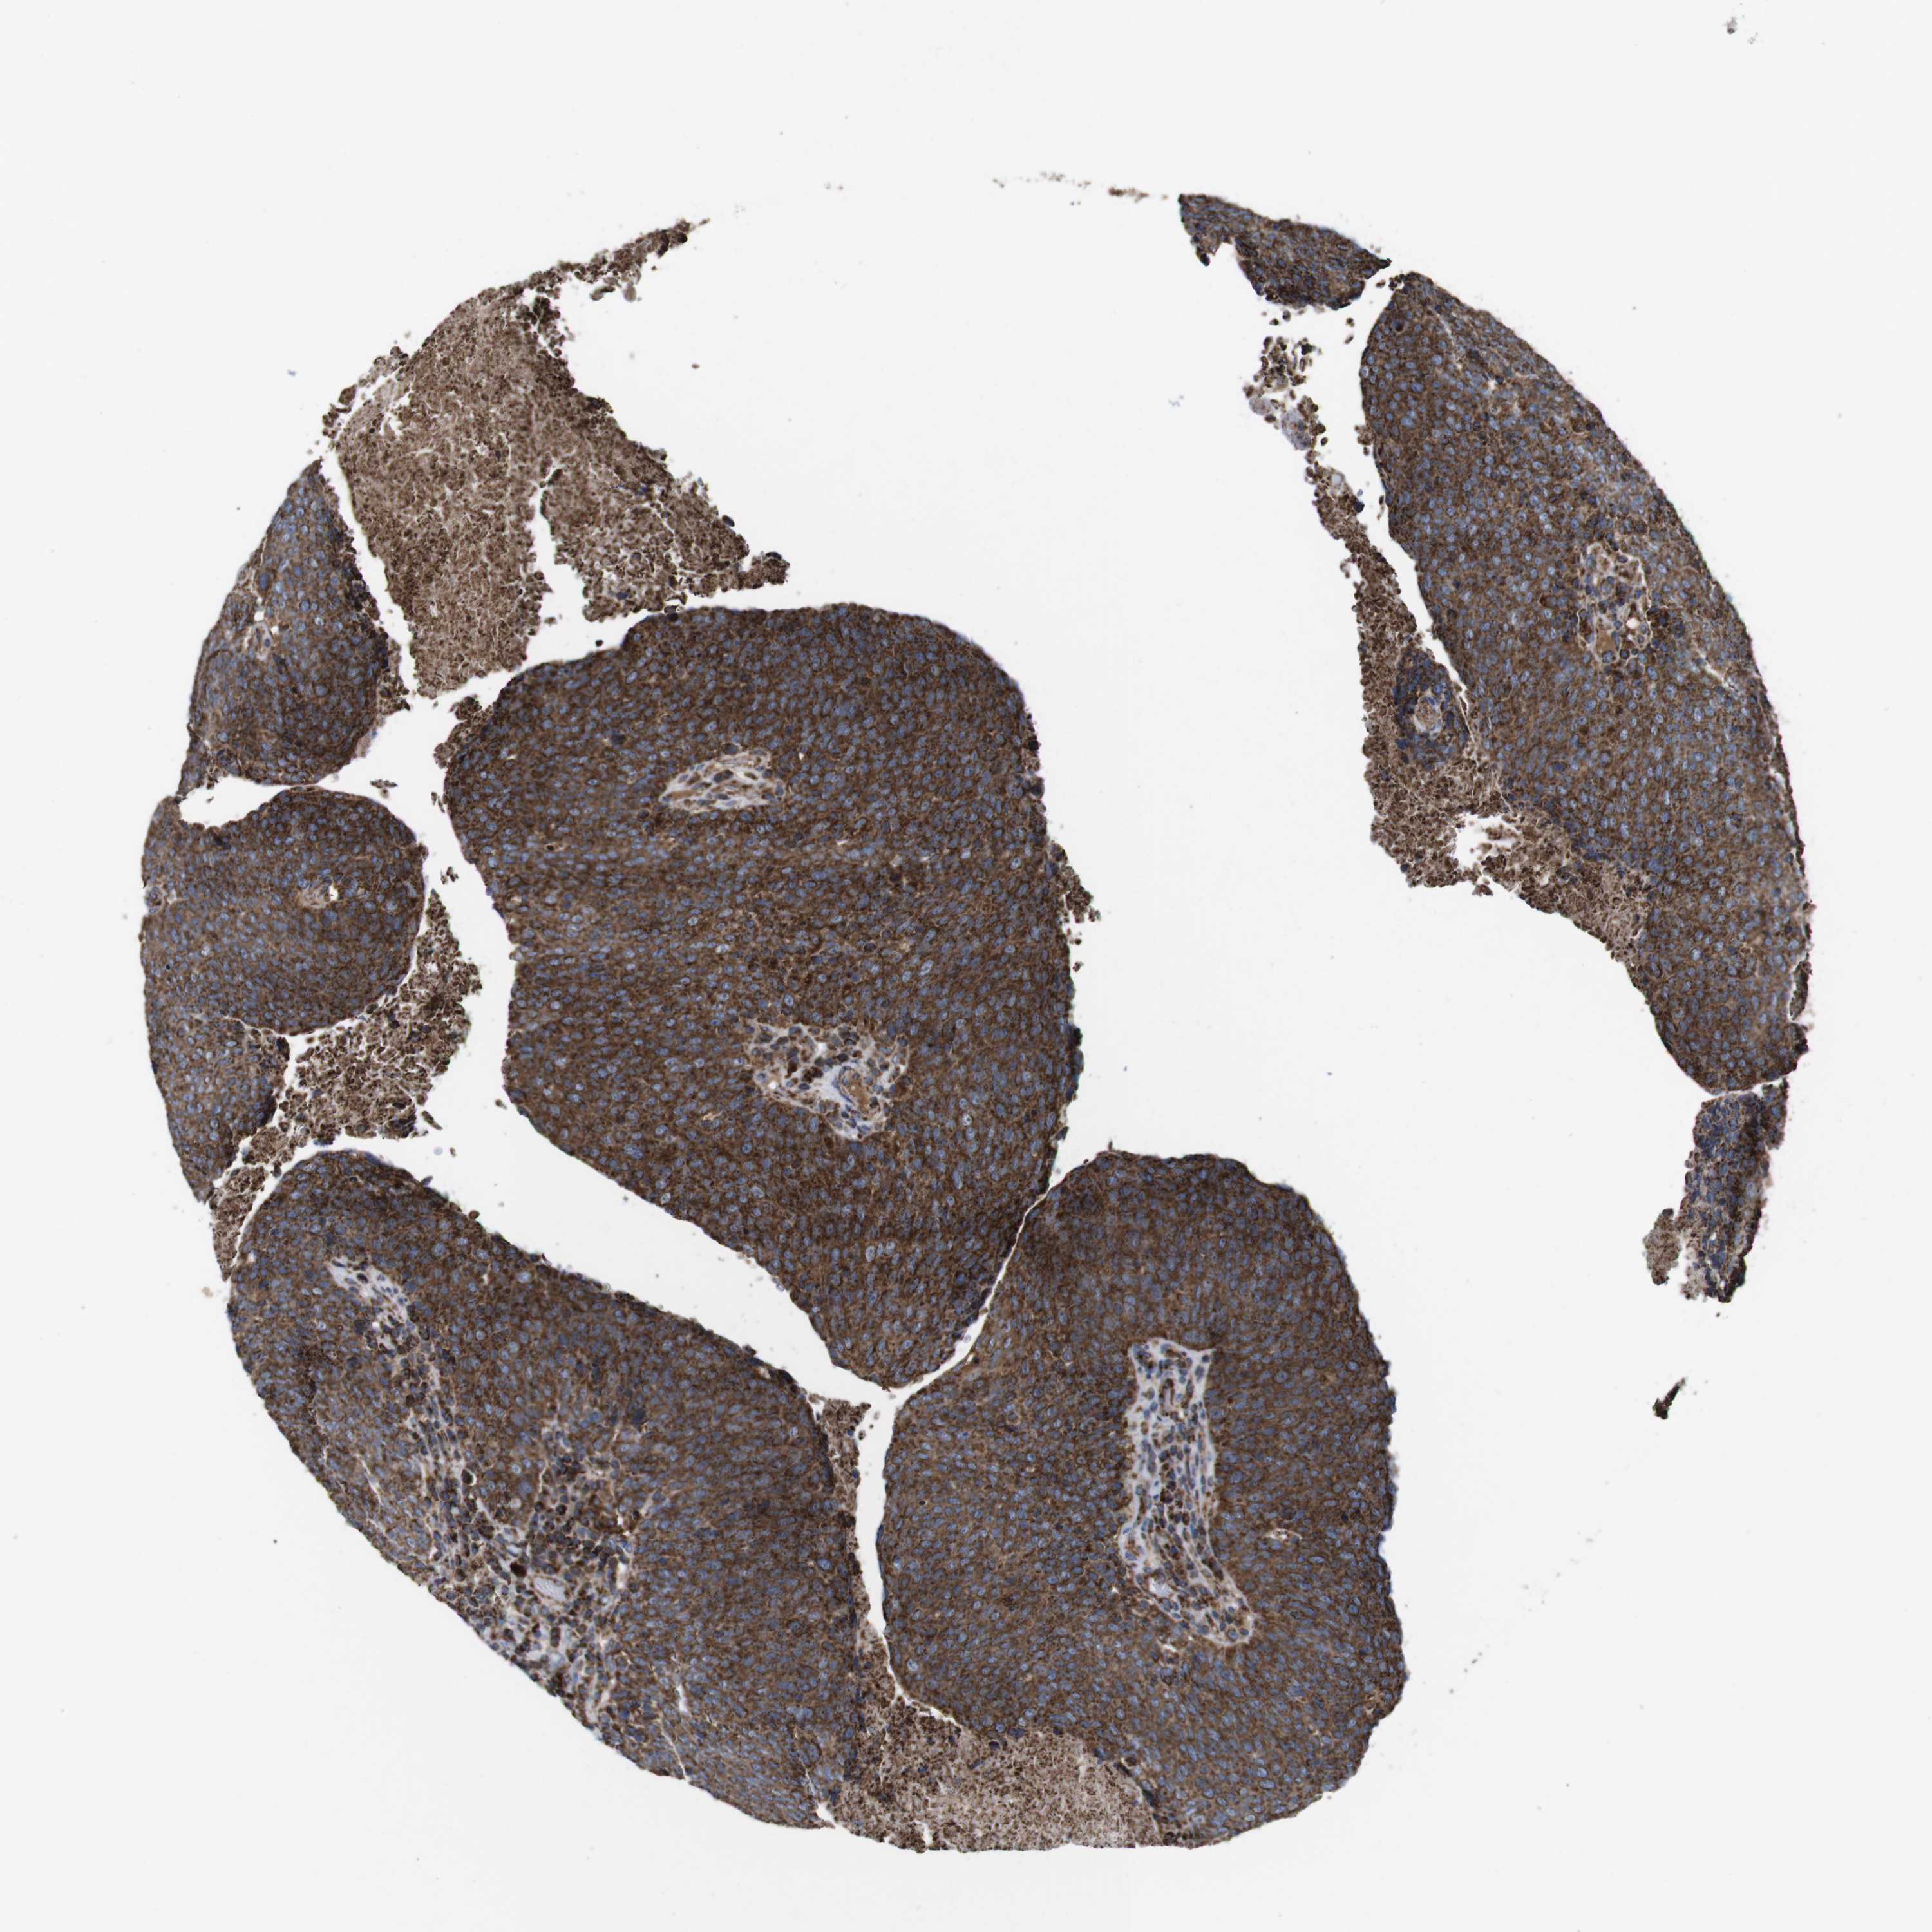

HEAD AND NECK CANCER - Protein expressioni

A mouse-over function shows sample information and annotation data. Click on an image to view it in a full screen mode. Samples can be filtered based on level of antibody staining by selecting one or several of the following categories: high, medium, low and not detected. The assay and annotation is described here.

Antibody stainingi

Antibody staining in the annotated cell types in the current human tissue is reported as not detected, low, medium, or high, based on conventional immunohistochemistry profiling in selected tissues. This score is based on the combination of the staining intensity and fraction of stained cells.

Each image is clickable and will lead to virtual microscopy that enables deeper exploration of all samples and also displays staining intensity scores, fraction scores and subcellular localization as well as patient and tissue information for each sample.

Antibody HPA007043

Antibody HPA007044

Antibody CAB010052

Staining

High

Medium

Low

Not detected

Squamous cell carcinoma, NOS

Adenocarcinoma, NOS

Adenoma, NOS

Squamous cell carcinoma, metastatic, NOS